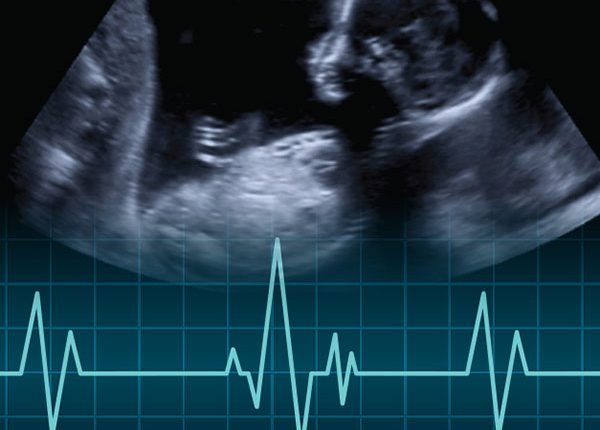

ضربان قلب جنین و تعیین جنسیت

تغییرات جالبی در هفته 12 بارداری برای سیستم گردش خون جنین به وجود می آید، در این زمان مغز استخوان جنین شروع به تولید سلول های خونی می کند. در هفته 17 بارداری، مغز جنین شروع به تنظیم ضربان قلب می کند تا او را برای زندگی در دنیای خارج از رحم آماده کند. (تا این مرحله، قلب به طور خودکار می تپد)

در طی سه هفته بعد، تقریبا در هفته 20 بارداری می توان صدای ضربان قلب جنین را با استفاده از استتوسکوپ (گوشی معاینه) شنید.

پزشک ممکن است در صورت نیاز به شنیدن و بررسی بهتر ضربان قلب جنین، از هفته 18 تا 24 بارداری برای مادر اکوکاردیوگرافی که سونوگرافی ویژه ای برای ارزیابی قلب جنین است، توصیه کند. (این کار در صورت داشتن سابقه خانوادگی نقایص قلبی یا ابتلا به دیابت، فنیل کتونوری یا بیماری خود ایمنی لازم است).

در این زمان قلب جنین در هر دقیقه حدود 140 ضربان دارد. حدود هفته 25 بارداری، مویرگ ها (کوچک ترین رگ های خونی) شکل می گیرند و پر از خون می شوند.